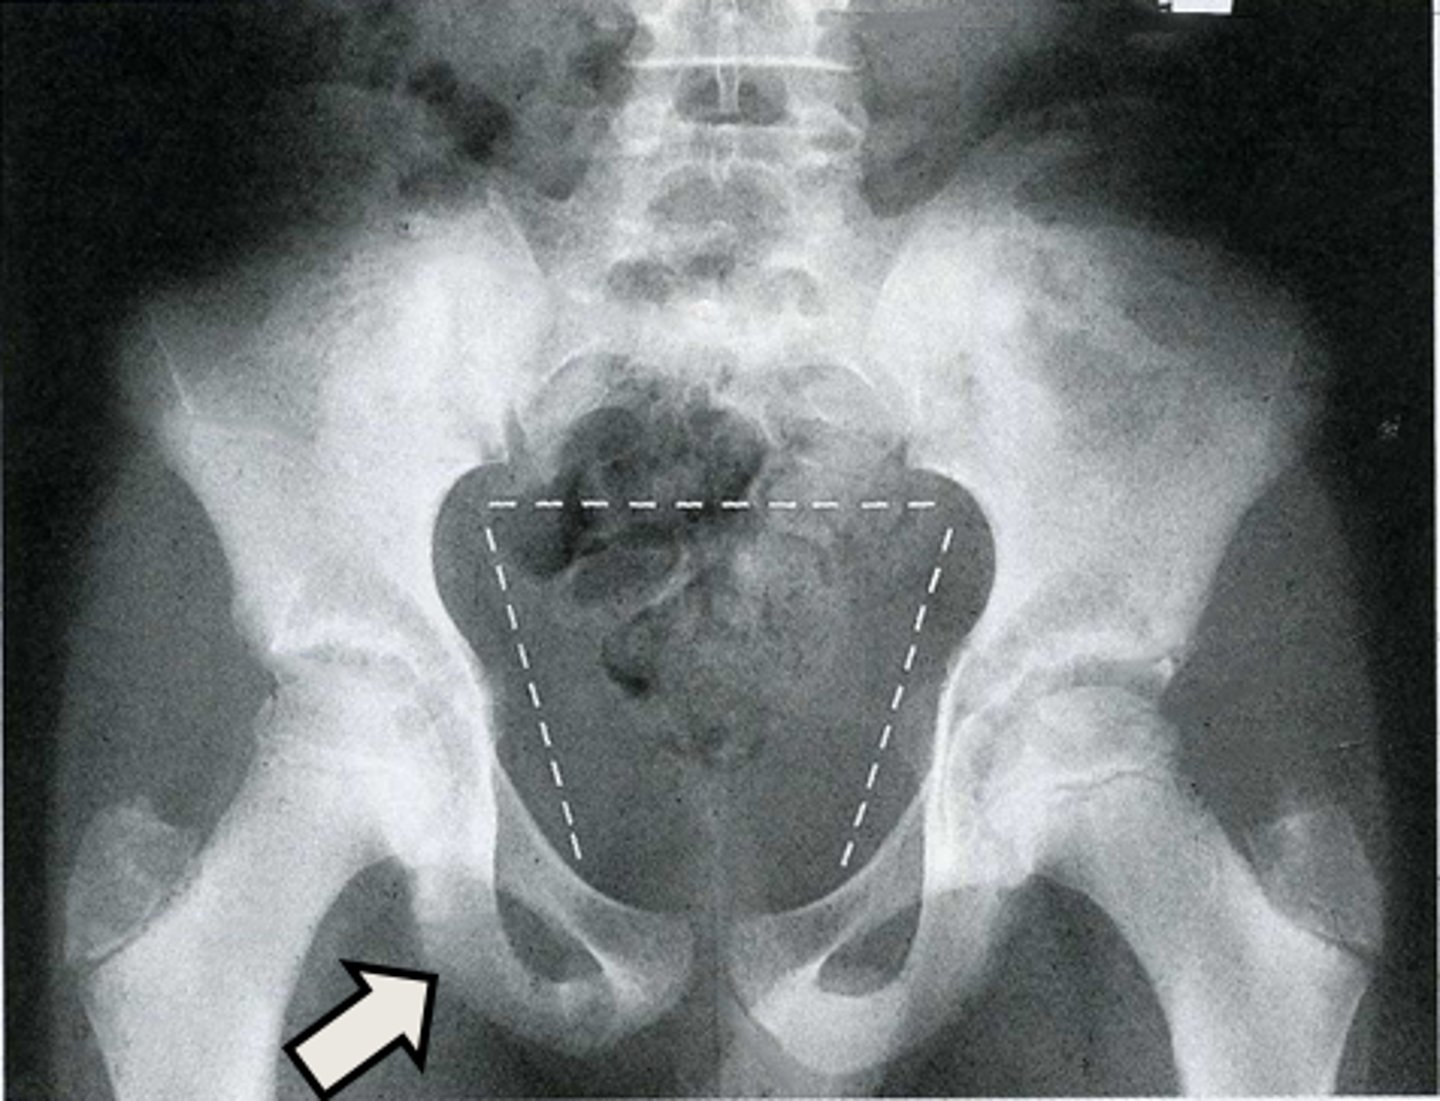

AP pelvis

What is the image?

Acetabulum

What is indicated in the image?

Body of L4

Epiphysial plate

Femoral head

Hip joint

Ilium

Ischial spine

Ischial tuberosity

Nonfused greater trochanter

Obturator foramen

Pubic symphysis

Sacroiliac joint

Sacrum